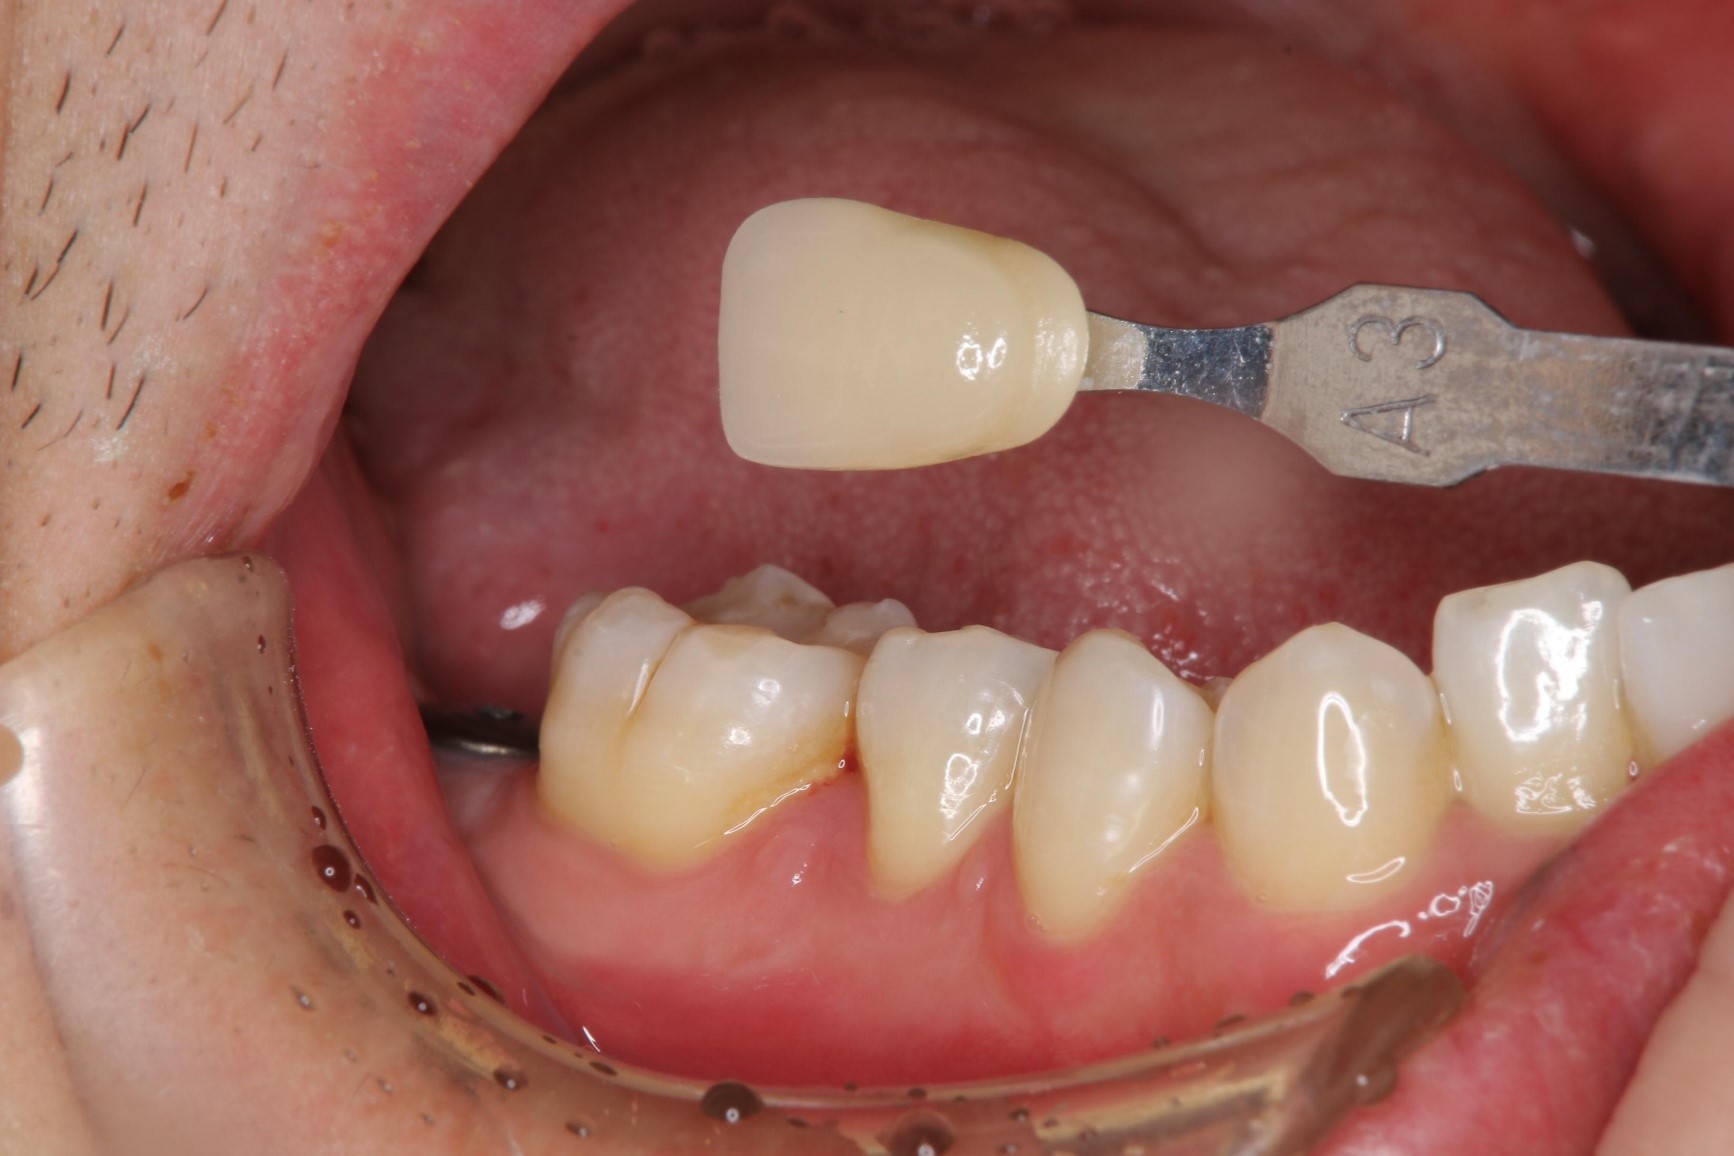

照相比色